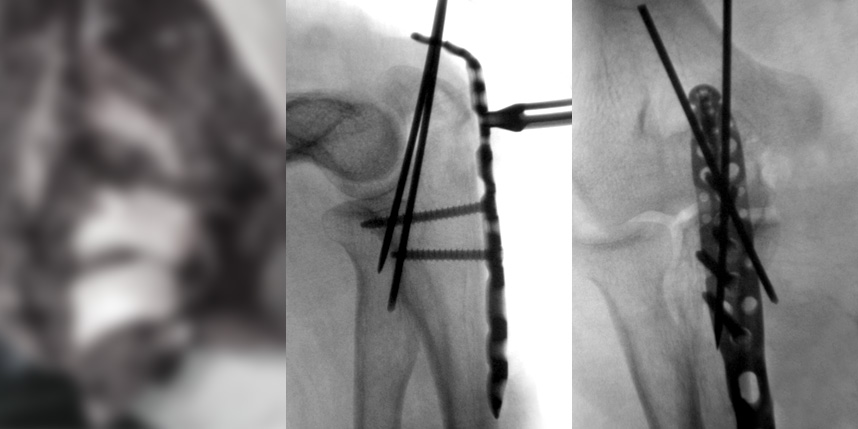

골절은 정확하게 골절편을 잘 맞추고 고정하는 것이 중요합니다. 특히 관절면을 잘 맞추는 것이 중요합니다.

또한 수술 이후 빠른 재활을 통해 전체적인 회복을 도모하여 일상으로 빨리 복귀할수 있도록 해야 합니다.

* 환자에게 받은 소중한 자료입니다.